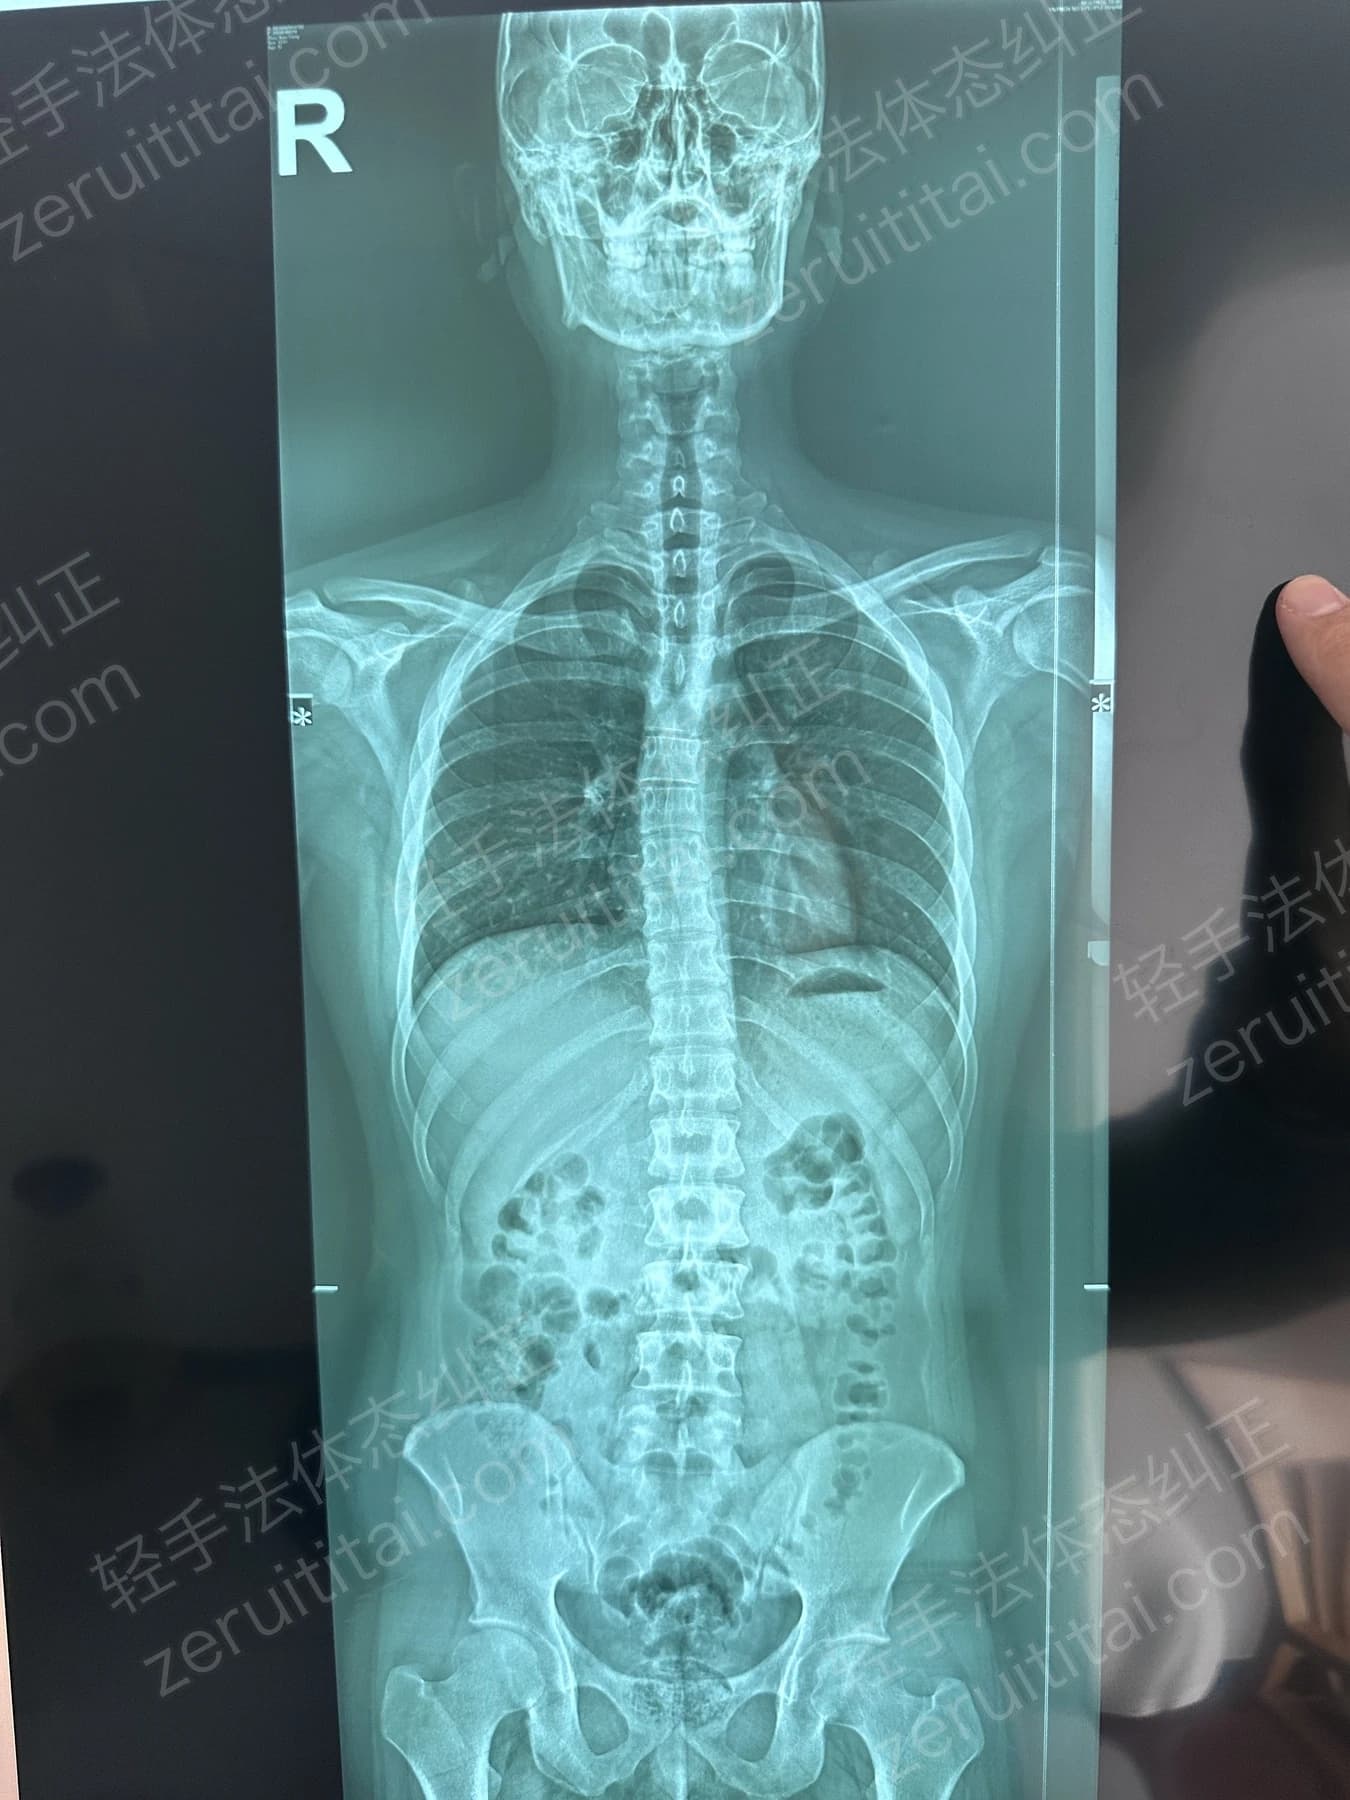

2022.12.26

第 3 次记录